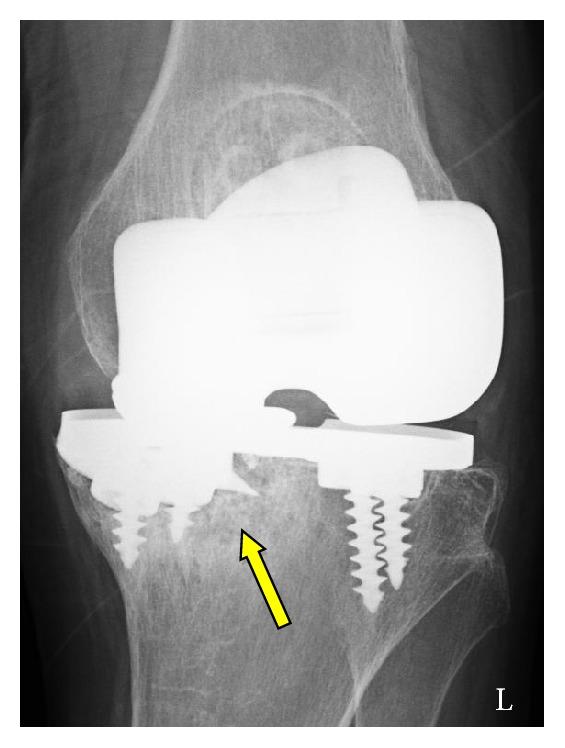

We report a rare case of tibial baseplate fracture of Miller-Galante II (MG II) prosthesis. We examine the factors that may cause such late fracture and review the literature on radiographic analysis and retrieval studies. A 76-year-old woman, who had undergone bilateral MG II total knee arthroplasty due to rheumatoid arthritis 16 years earlier, presented to our department with a 3-month history of left knee pain. Plain radiographs revealed severe distortion of the medial tibial component. During revision knee arthroplasty, we observed severe metallosis in the knee joint, polyethylene insert deformation, and posteromedial coronal baseplate fracture. After removal of the fractured tray, a bone deficit due to osteolysis was noted. The revision prosthesis (LCCK, Zimmer-Biomet) was implanted uneventfully. Four months after revision surgery, the patient was ambulating and had no complications. The implants on the right side had survived without complications for 17 years. We speculate that the primary causative factor of the fatigue fracture of the base plate due to loss of bony support most likely secondary to osteolysis was varus malalignment at primary implantation. This case highlights the importance of paying close attention to the correct alignment of each component at primary implantation.